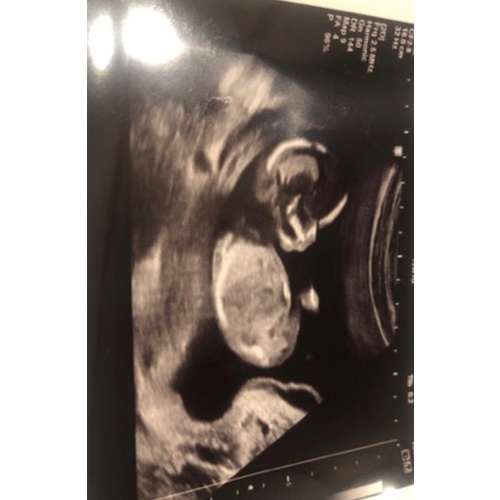

Bij 13w en 5 dagen zag je het ook vanaf zijkant en deze echo is 14w en 6 dagen

Ik was daar 14 weken en 6 dagen😊

Dit is mijn echo foto van vandaag, mijn vriendinnen heb ik een envelop gegeven met het geslacht en ik weet het zelf ook niet. Vraag me ook af of mensen het geslacht kunnen zien na aanleiding van deze echo.